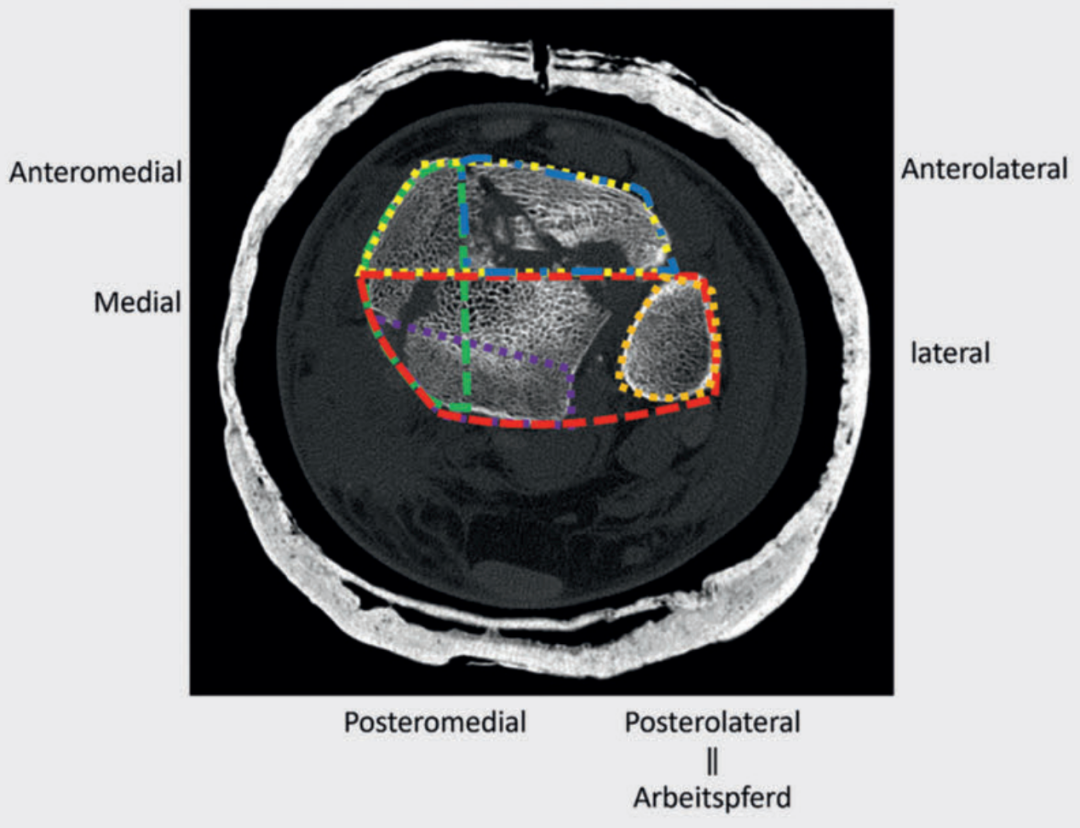

手术入路的选择需综合考虑软组织损伤情况、骨折形态,并结合 “四柱概念” 和 “骨折图谱概念”。在术前规划中,分析主要骨折线和次要骨折线至关重要。约90%的骨折可通过后外侧入路联合前方入路进行治疗。若因骨折形态特殊,需对骨折进行 360° 全方位固定,可将患者置于侧卧位,通过该体位可联合采用后外侧入路和扩大入路。

病例1在受伤后送往医院急诊,首先进行了跨踝关节外固定架。尽管患者初始存在Ⅱ度闭合性软组织损伤,但由于及时进行了复位并植入外固定架,未需实施筋膜间室切开术。在术前CT图像中,可清晰观察到3个主要骨折块及1个中央粉碎区。通过及时植入外固定架,可恢复关节位置,并有效避免软组织损伤进一步加重。